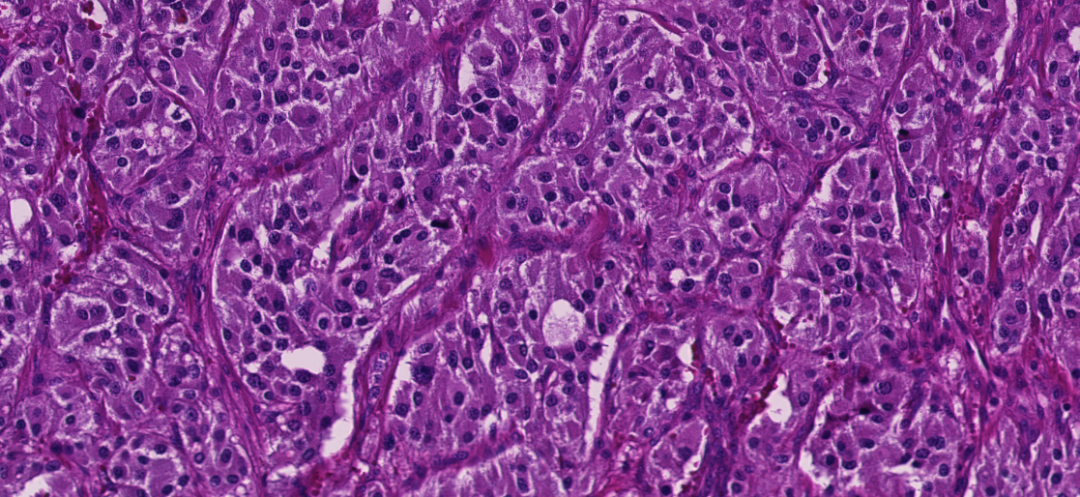

低倍镜下显示肿瘤富含血窦结构。

肿瘤细胞胞浆呈淡粉色,间质中可见丰富的纤细纤维血管束。

肿瘤细胞核形态为圆形或卵圆形,异型性不明显,核染色深,未观察到明显核仁。

- 生长模式: 典型的PGL呈现“Zellballen”(细胞球)样巢状结构,肿瘤细胞巢被纤细的毛细血管网分隔,巢周可见支持细胞。

典型的Zellballen样巢状生长模式 [引自第五版泌尿WHO]

- 细胞特点: 肿瘤细胞通常胞浆嗜酸性,核呈圆形或卵圆形。少数情况下可见核多形性或深染,需与尿路上皮癌、前列腺癌或肾细胞癌鉴别。

- 间质特点: 间质富含纤细的毛细血管网,支持细胞围绕在肿瘤细胞巢周围。